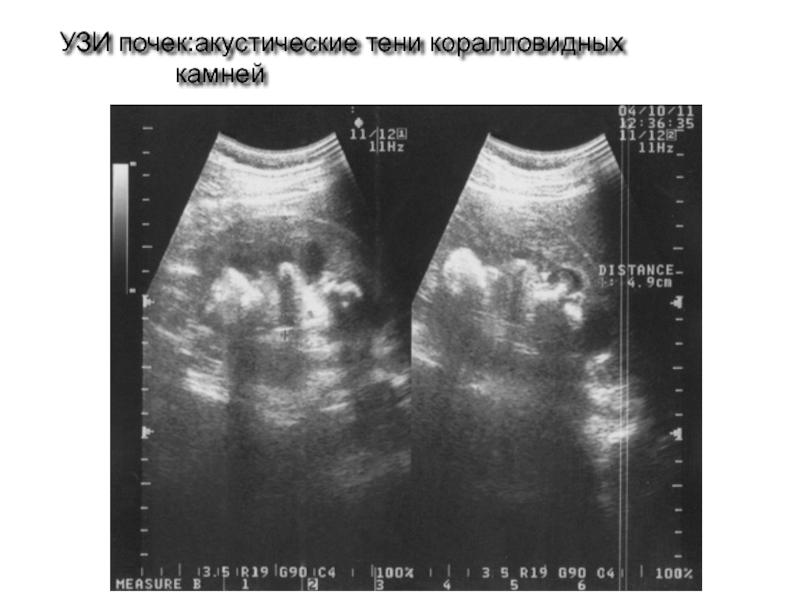

Слайд 61 УЗИ почек:акустические тени коралловидных камней